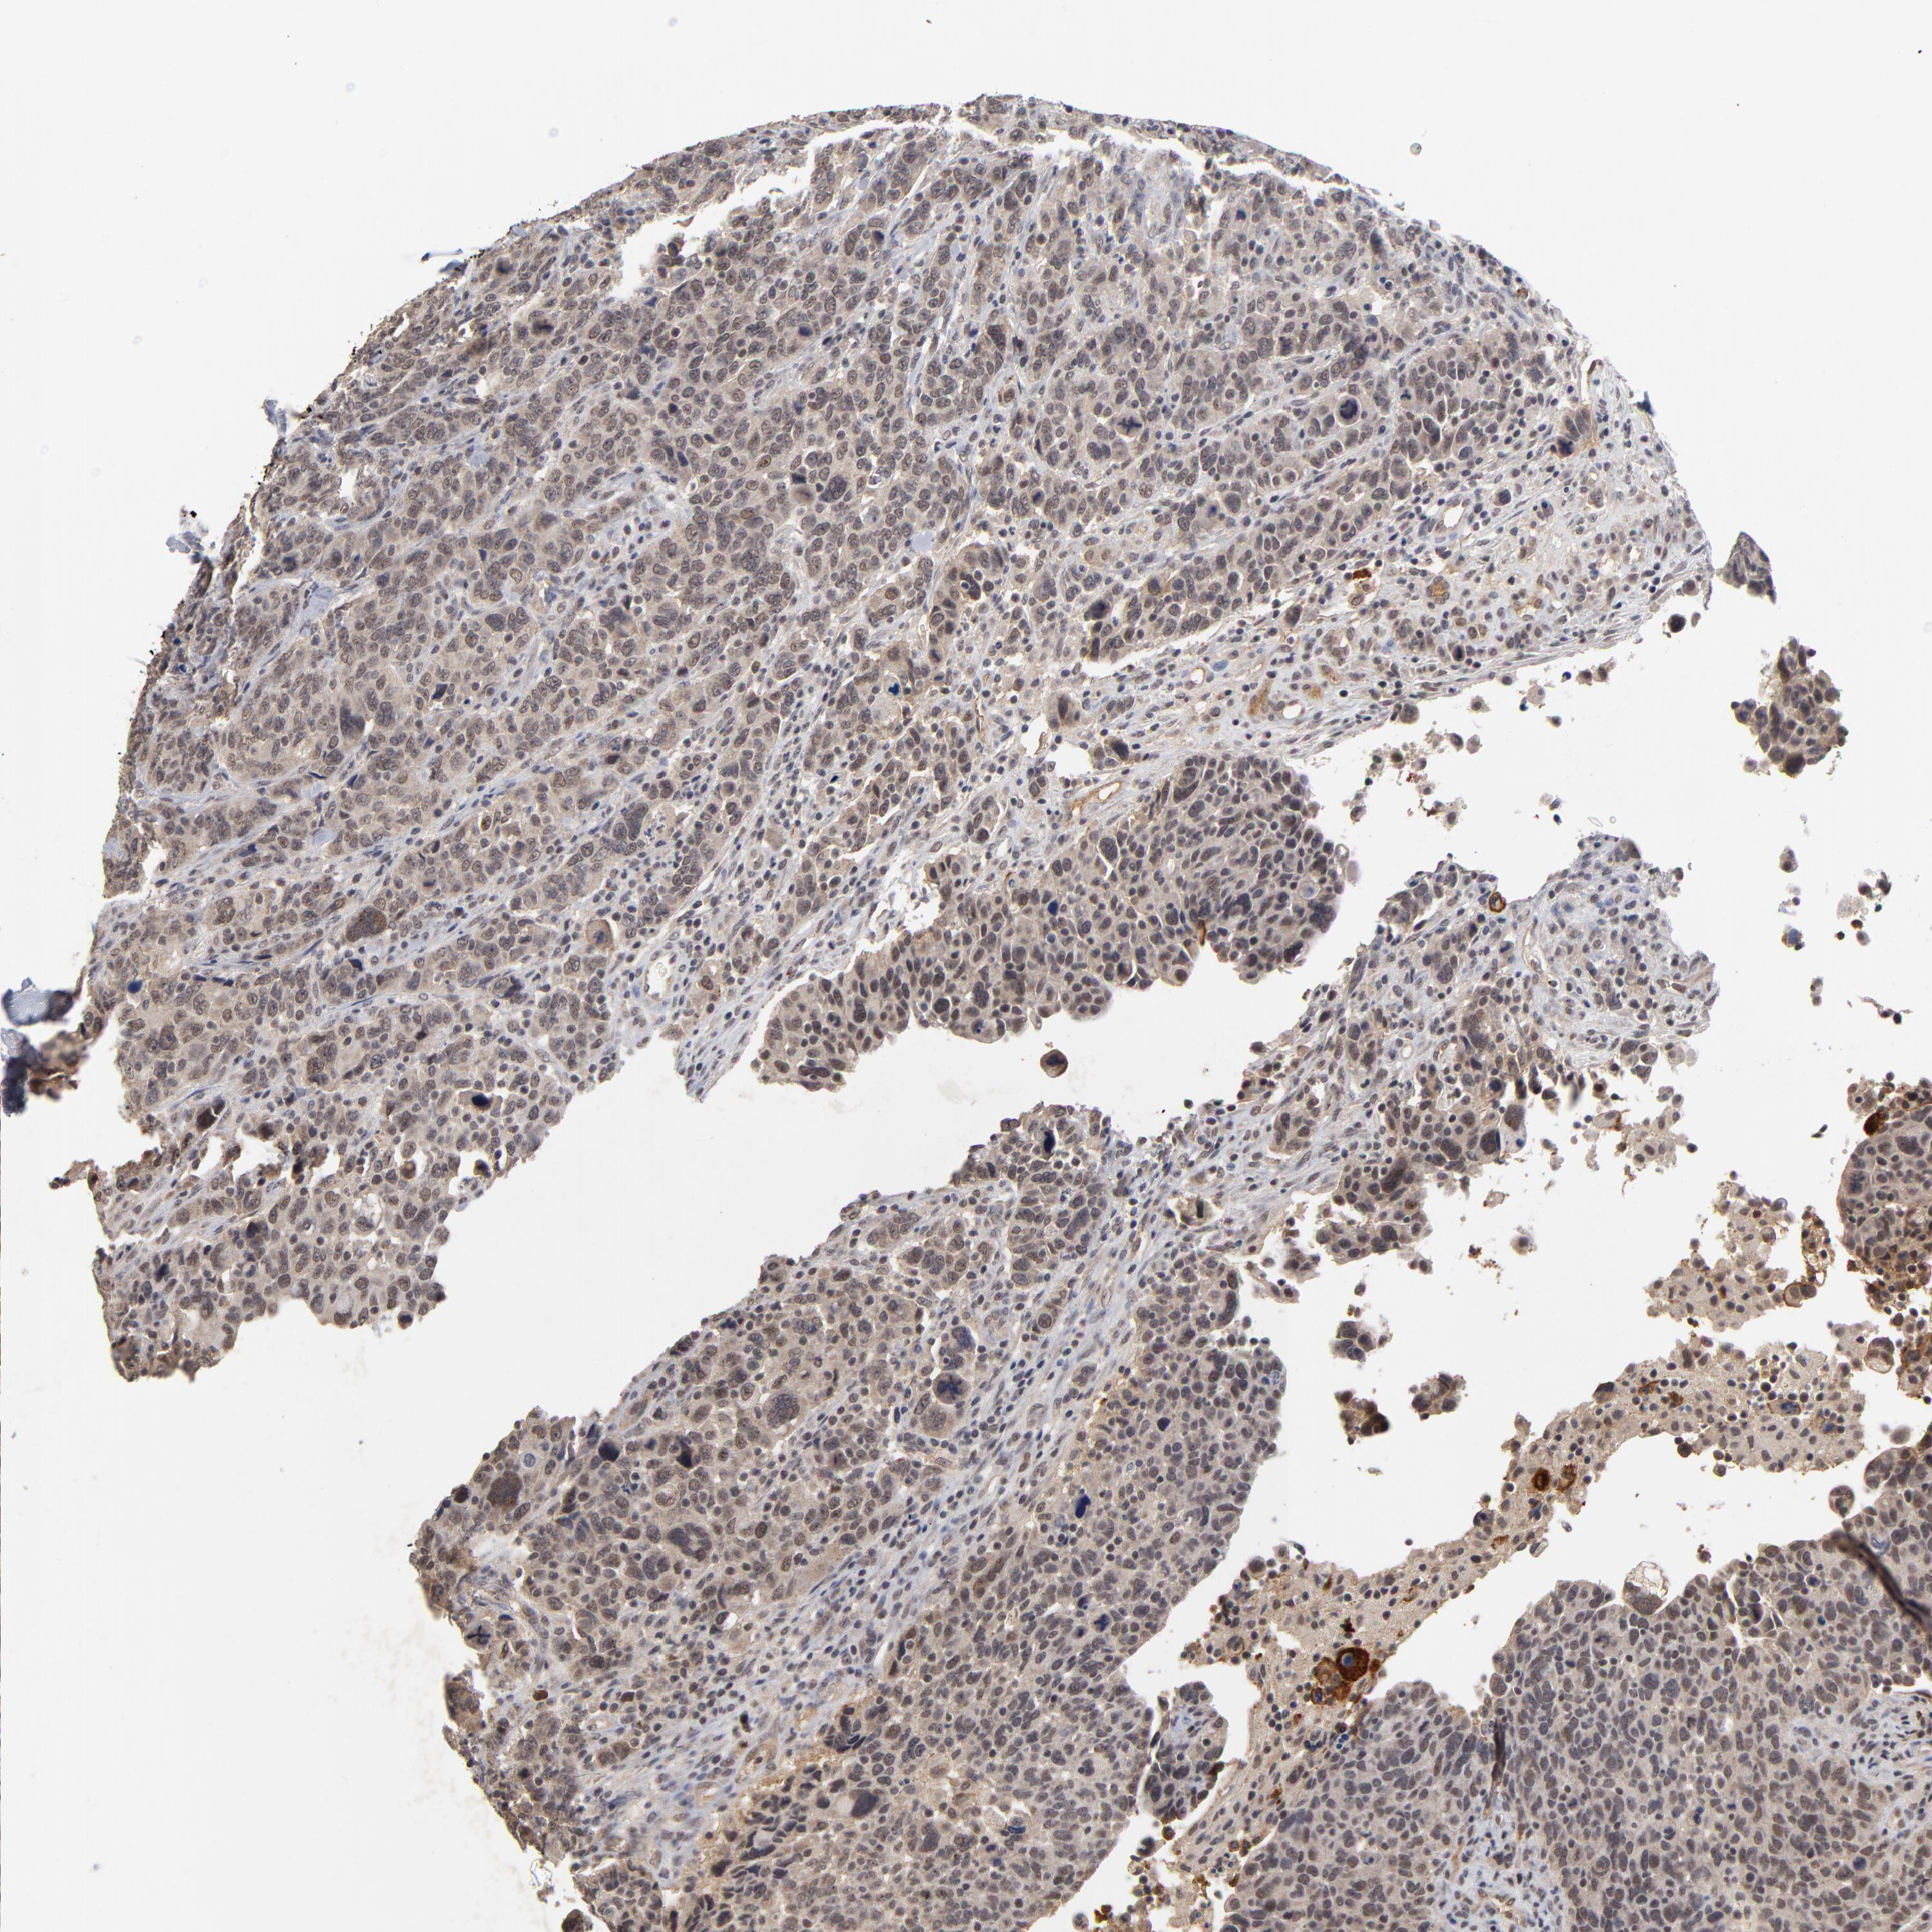

CANCER BREAST CANCER Show tissue menu

BRCA TCGA BRCA VALIDATION PROTEIN EXPRESSION